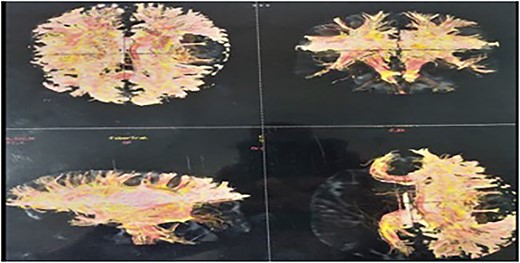

A tractography was also performed, showing destruction of the left superior longitudinal fasciculus, superior occipito-frontal fasciculus, and partial destruction of the left cortical spinal tract (Fig. 3). Gray and white matter differentiation was maintained and no abnormal signals were visualized in the rest of the cerebral hemispheres. There was subtle contrast enhancement.

Tractography showing destruction of the left superior longitudinal fasciculus, superior occipito-frontal fasciculus, and partial destruction of the left cortical spinal tract.